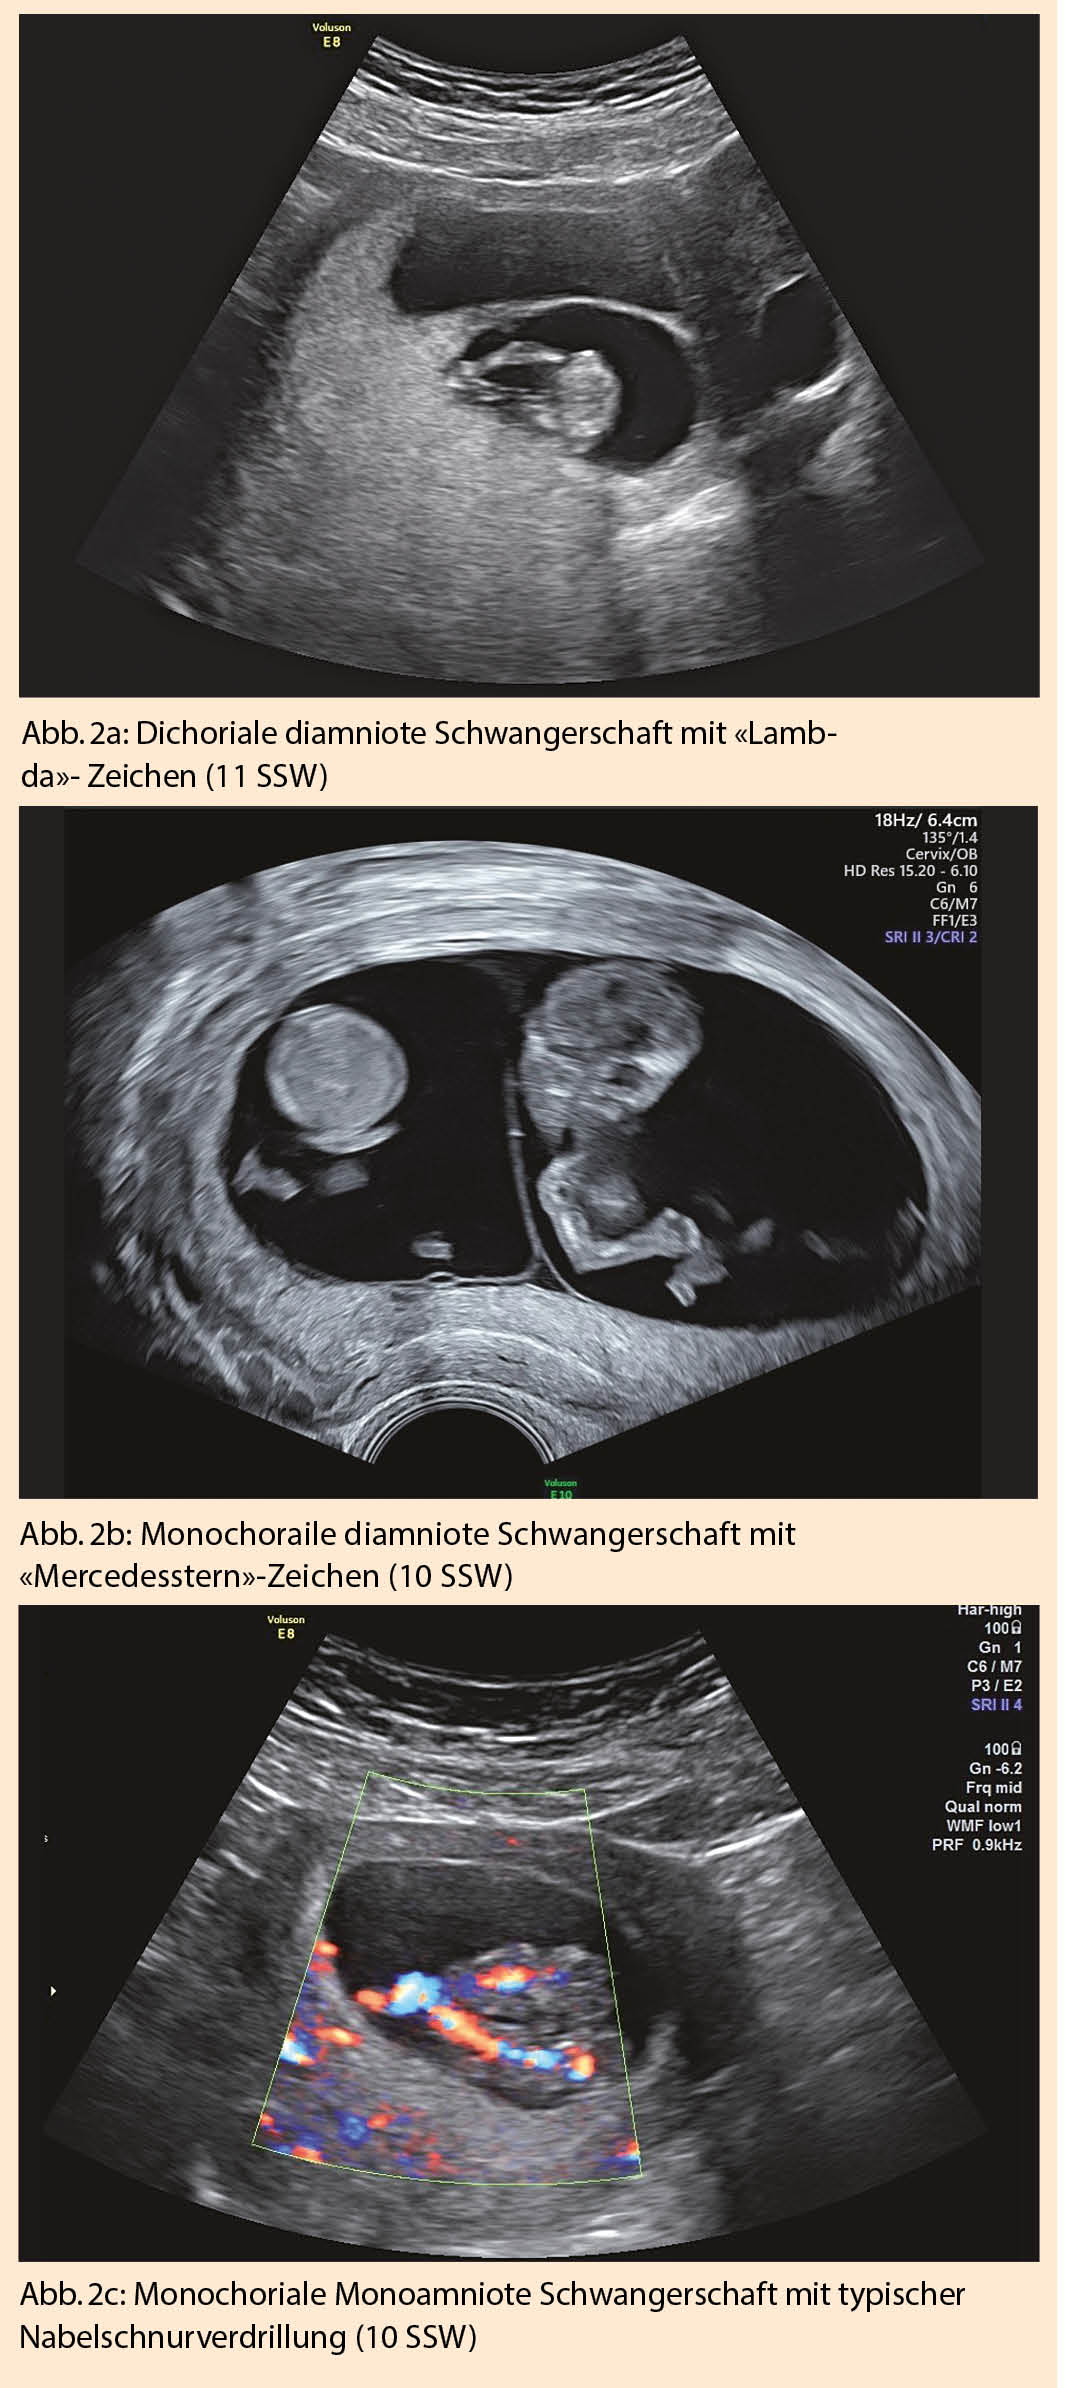

Sieht man sonographisch zwei klar getrennte, von Throphoblast umgebene Fruchthöhlen, liegt eine dichoriale diamniote Schwangerschaft vor. Um 12-14 SSW entwickelt sich daraus das typische «Lambda»-Zeichen (Abb. 2a), da nur noch plazentaseitig ein Choriondreieck zwischen die beiden Amnionblätter zieht. In 7% verschwindet das Lambda-Zeichen nach 20 SSW (10).

Findet sich nur eine Fruchthöhle mit zwei Embryonen, liegt eine monochoriale Zwillingsschwangerschaft vor. Bei monochorialen diamnioten Zwillingen liegen die beiden Amnionblätter glatt aufeinander und bilden so eine feine Trennwand zwischen den Feten. Bei 8-10 SSW sind die beiden Amnionblätter meist noch etwas vom Chorionblatt abgelöst, wodurch sonographisch der Eindruck eines leeren «Lambda»-Zeichens oder auch das typische Bild eines «Mercedesstern»-Zeichens erscheint (Abb. 2b). Sobald die Amnion- und Chorionblätter vollständig verschmelzen bildet sich das «T»-Zeichen.

Vor 8-10 SSW ist die Amniozität oft noch schwierig zu beurteilen. Die Dottersackdiagnostik hilft hierbei auch nicht weiter. Bei einer Monoamnionizität, ca. 4% aller monochorialen Schwangerschaften, lässt sich auch bei 10-14 SSW keine Trennwand zwischen den Embryonen darstellen. Typischerweise zeigt sich eine Amnionhöhle mit zwei eng zusammenliegenden Nabelschnuransätzen oder einer Nabelschnurverdrillung (Abb.  2c). Die Messung der Membrandicke und das Zählen der Membranschichten zwischen den Feten sind keine zuverlässigen Diagnosekriterien (10).